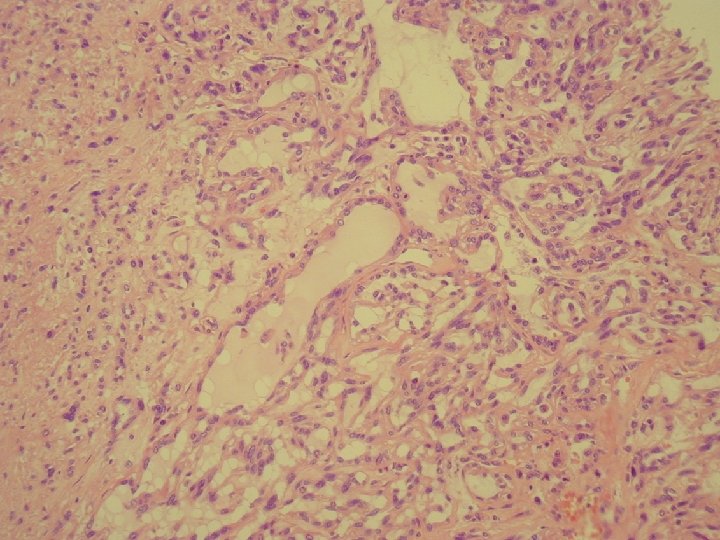

Klinické údaje: • 76 -ročný muž sledovaný pre tumor močového mechúra, na CT zachytený tumor pravej obličky priemeru 4 cm • makro: sivočervený, dobre ohraničený, s drobnými dutinkami, subkapsulárny

Imunohistochémia • pozit. : EMA, M 903, Vimentin (fokálne) P 504 S, AE 1/3 • negat. : CD-10, RCC, SMA, Dezmín, HMB-45, CEA, CK 7

Mucinous tubular and spindle cell carcinoma.

• LG polymorfný renálny tumor: mucinózny, tubulárny, spindle cell • 17 – 82 rokov • M/Ž– 1/4 • v minulosti: neklasifikovaný alebo sarkomatoidný

Histogenéza • distálny nefrón, Henleho kľučka • proximálny nefrón, vzťah k papilárnemu Ca • ?